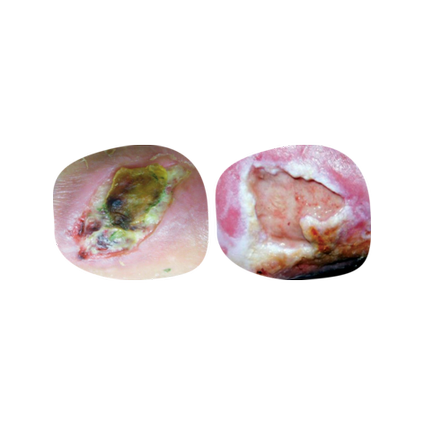

An optimal moisture balance is essential for wound progression, which requires continual evaluation. A balanced wound environment supports growth factors, cytokines, cell proliferation and migration.1-4

Assess the wound to identify the right treatment or intervention